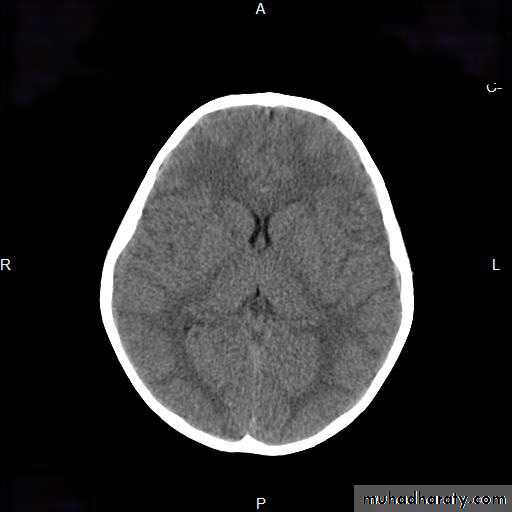

CT-SCAN OF BIH (NORMAL CT)TREATMENT